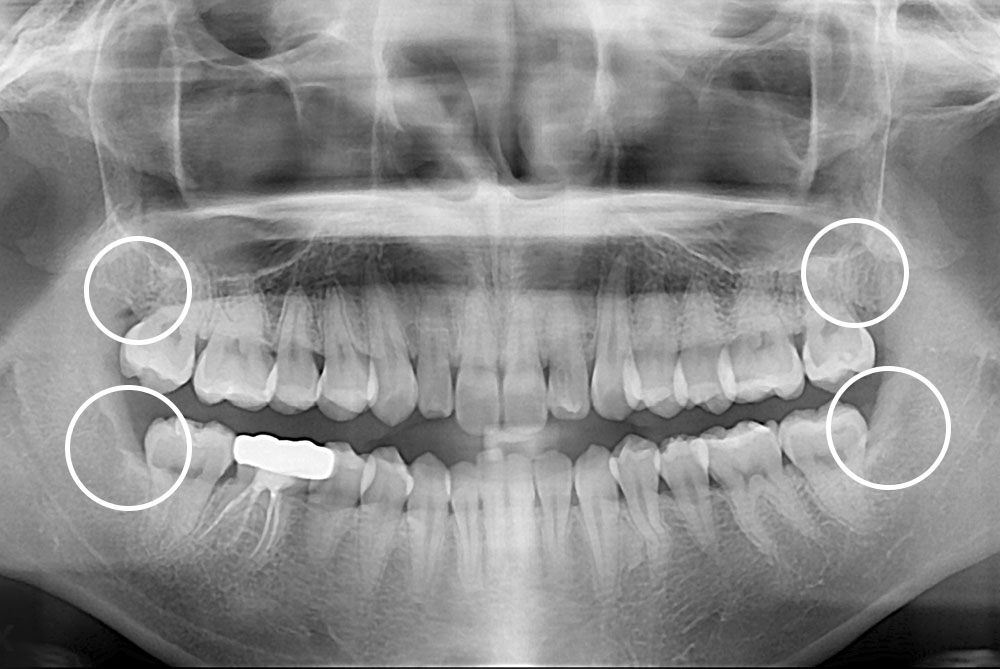

[사랑니] 매복 사랑니 발치

치료후 : 2019-10-14

세종치과는 구강악안면외과학 박사이신 원장님이 발치하는 치과입니다.